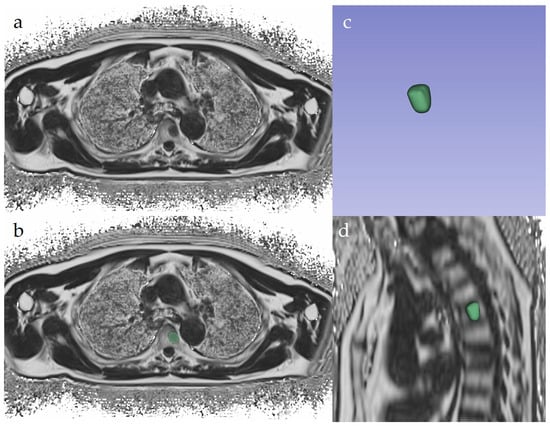

2.3. Image Segmentation